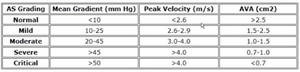

- Severity by continuous wave (CW) Doppler peak velocity (m/s)[2]

- AS is unlikely if peak CW velocity well below 2.5 m/s, and AVA measurements may not be necessary

- < 2.5 = aortic sclerosis

- 2.6 - 2.9 = mild

- 3.0 - 4.0 = moderate

- > 4.0 = severe

- Aortic stenosis valve area severity[3]

- Normal, > 2.5 cm²

- Mild, 2.5 - 1.5 cm²

- Moderate, 1.0 - 1.5 cm²

- Severe, < 1.0 cm²

AS Measurements and Grading